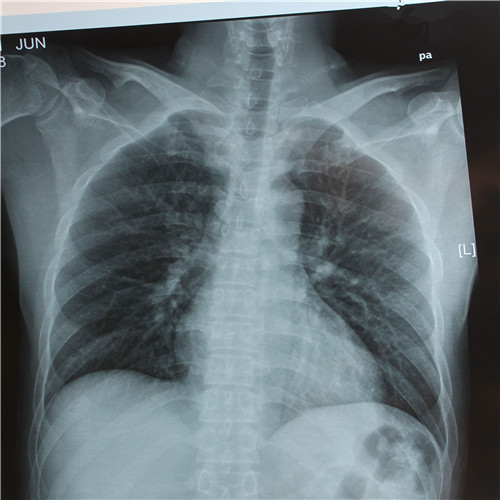

呼吸道感染胸腔積液胸片下觀察

呼吸道感染胸片檢查